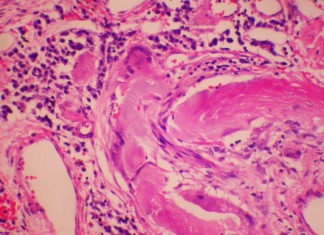

Nuevos avances en el tratamiento de los pacientes con cirrosis

Nuevos datos de los estudios clínicos presentados por primera vez en el Congreso Internacional de 2013 proporcionan nueva lógica para una opción de edad...